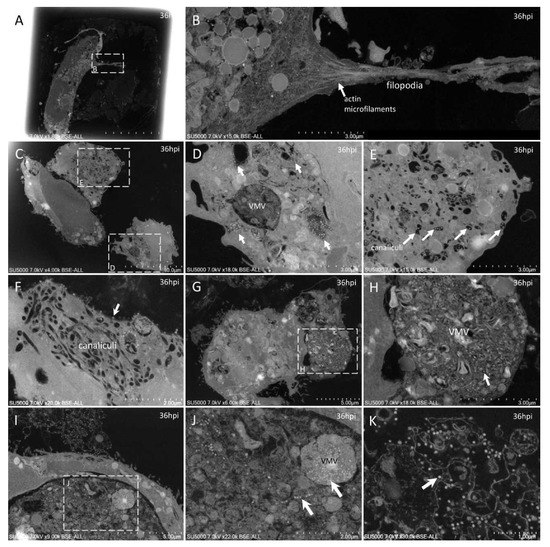

3. Results